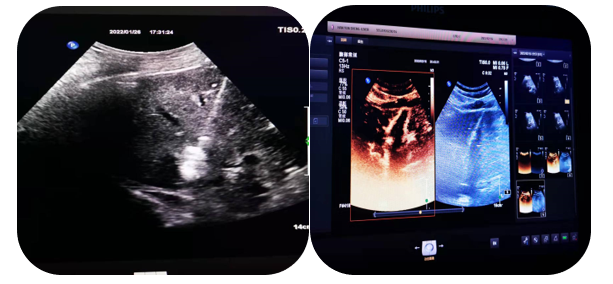

4.超聲介導(dǎo)下肝占位射頻及微波消融術(shù)

通過射頻電極發(fā)出高頻率射頻電流,電能使局部組織發(fā)生正負離子震蕩,并摩擦生熱達100°左右,熱能逐漸傳導(dǎo)至周圍組織,形成一個預(yù)定的球形或類球形的消融區(qū),腫瘤局部因高溫而發(fā)生凝固壞死。以達到和手術(shù)切除同樣的目的和效果。